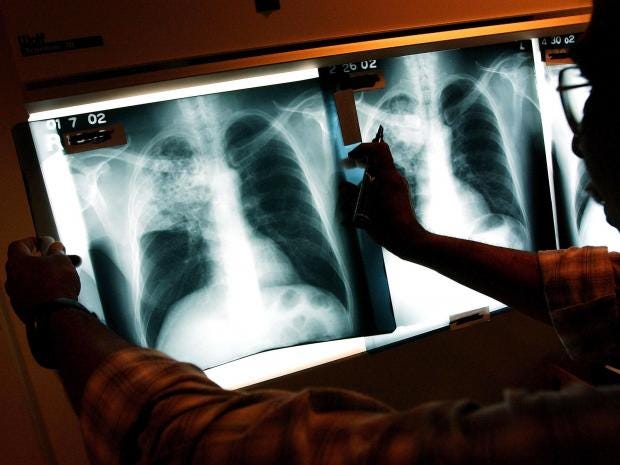

Global TB epidemic prompts fresh warnings amid drug-resistance crisis

The world is making “dismal progress” towards ending the global epidemic of tuberculosis – the infection which kills more people than any other – amid a “crisis” in resistance to drugs used to treat the disease, the World Health Organisation has warned.

An estimated 10.4 million people had TB last year with 1.8 million dying as a result, the WHO said in a new report.

One significant problem is that the bacteria that causes TB is gaining resistance to the drugs used against it. Some 480,000 people had a multi-drug resistant form of the disease last year.

The report said that multi-drug-resistant TB “remains a public health crisis” with an estimated 480,000 people catching it in 2015, about the same level as 2014.

Nearly half of all cases of multi-drug-resistant forms of TB occurred in three countries: India, China and Russia.